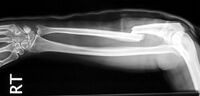

|Bilder=[[Datei:Gebrochene_Speiche.jpg|thumb|200px|center|Gebrochener Arm - Speiche]]}}

|Bilder=[[Datei:Gebrochene_Speiche.jpg|thumb|200px|center|{{ImageCaption|Titel=Gebrochener Arm - Speiche|Urheber=Jane Agnes |Quelle={{ImageMetaSource|Quelle=https://commons.wikimedia.org/wiki/File:Monteggia_Fracture.jpg|Linktext=commons.wikimedia.org}}|Lizenz={{ImageMetaLicense|URL=https://creativecommons.org/licenses/by-sa/3.0/deed.en|Lizenz=CC BY-SA 3.0}}}}]]}}

Gebrochener Arm - Speiche - Jane Agnes commons.wikimedia.org, CC BY-SA 3.0

Knochenbrüche werden auch Frakturen genannt. Die entstehen durch direkte (zB Tritt) oder indirekte (zB Sturz) Gewalteinwirkung.

Dadurch kommt es meist zu einer Verschiebung der Bruchenden und dadurch zu einer mehrwöchigen Pause für die betroffene Person.